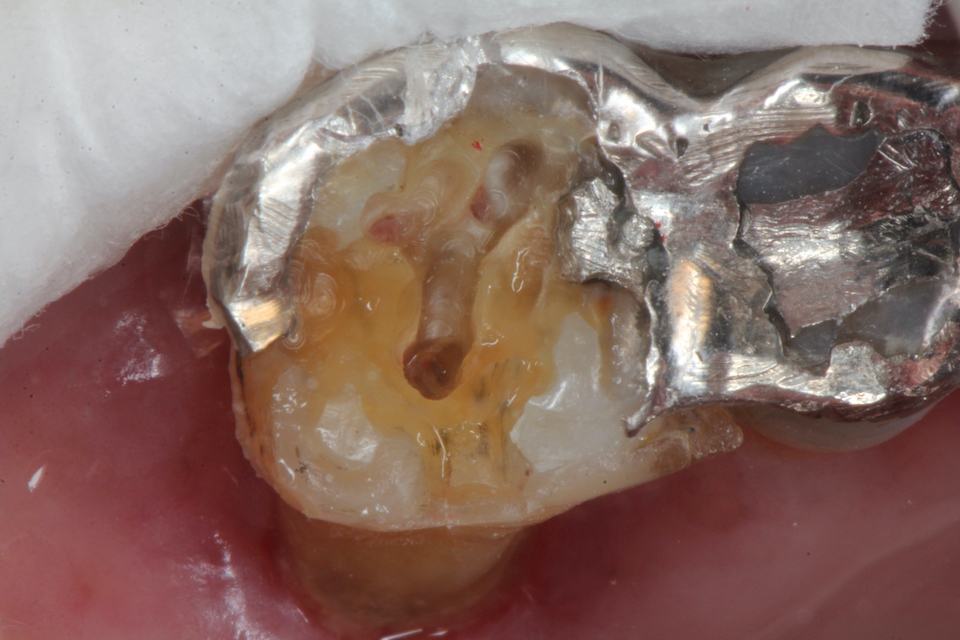

ボスミン液で止血した後は3MIX+α-TCPで根管充填というか直接覆髄というのか、露出している歯髄と根管内を覆うというか注入すればよい。それも緊密充填である必要もない。人間の歯髄というものは非常に丈夫なので炎症があれば全部取る必要があるというのは、これも嘘だ。

α-TCPで充填

CRで漏洩しないようにカバーして終わり。これで痛みや強烈な沁みは消失する。こんな簡単なことで歯髄炎が治るとか信じられないかもしれないが、これが事実だ。冠を被せるまで何度も患者を通わせるなどという患者を苦しめる必要はない